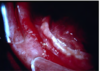

What is this radiographic & clinical findings?

Periapical cyst

shows inflammation at site

abscess developed fistula tract thru

soft tissue. Pt will have pain until

pressure is released